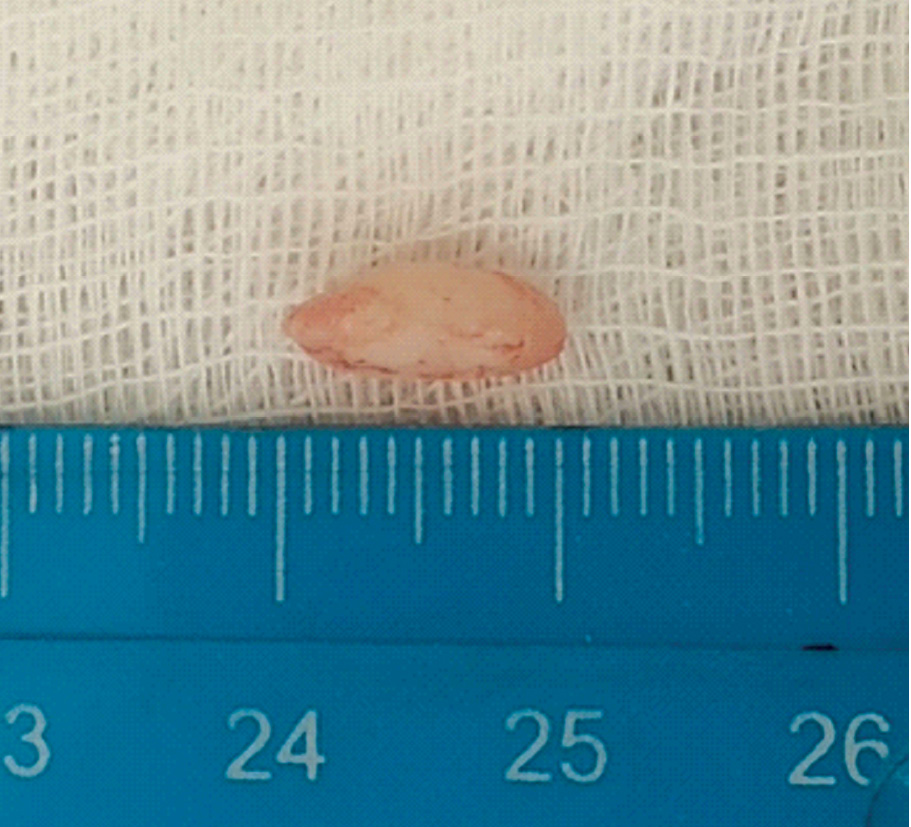

При поступлении в отделение оториноларингологии: общее состояние удовлетворительное. При эндоскопии полости носа после удаления слизи из общего носового хода слизистая оболочка левой половины носа розового цвета, умеренно отечная, в области дна полости носа слева в передних отделах с переходом на перегородку носа отмечается дефект диаметром 0,3 см слизистой оболочки с наличием беловатого твердого неподвижного выступающего образования (рисунок 1).

Рисунок 1. Эндоскопия полости носа. / Figure 1. Endoscopy of the nasal cavity.